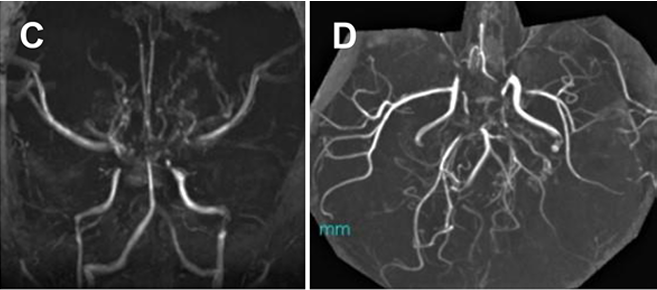

但在太一初次左侧手术后,另一例又发生了脑梗死,且远离搭桥的区域,这一不寻常的病程引起川岛教授的警惕。

图E:左侧联合搭桥手术后进行的弥散加权 MRI 显示远离搭桥的区域发生意外脑梗死。

图F:DNA序列分析,鉴定了杂合子c.12185G>A (p.R4062Q)变体(在色谱图中由 R 表示 G>A 替换)。

基因检测结果,二次手术与长期管理

在对太一进行相关遗传学检查后发现,他竟然携带 c.12185G>A (p.R4062Q) 的杂合子变异体,这是 RNF213 变异中较为明确的 MMD 易感变异之一。